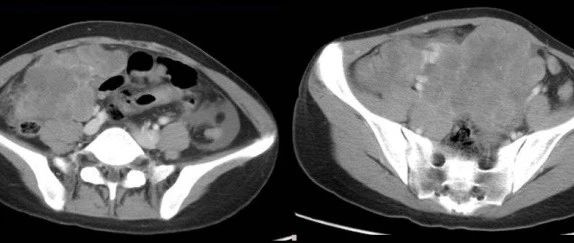

青年女性,腹痛3天,请诊断!

医学影像  yxyx-app  医学影像APP,打造伴随医生快速成长的影像学习社区。与影像园(Xctmr.com)一起提供最全面的影像案例库、基础(解剖、病理、影像诊断)知识、影像技术及考题等,为医生提供最佳的医学影像参考。【所属科室】消化科【基本资料】患者,女,19岁【主诉】腹痛3天【现病史】患者3天前无明显诱因下出现腹痛,位于脐周左右,呈阵发性,性质不明,伴有恶心呕吐,多由咳嗽引起大便呈稀水样,色黄,2次/日。近期症状加重。...